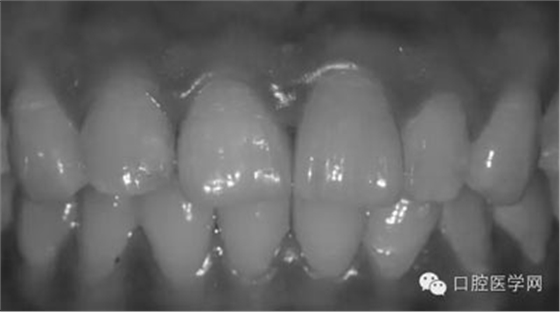

1、術(shù)前比色照

將比色照飽和度調(diào)到最低有助于牙齒明度的選擇